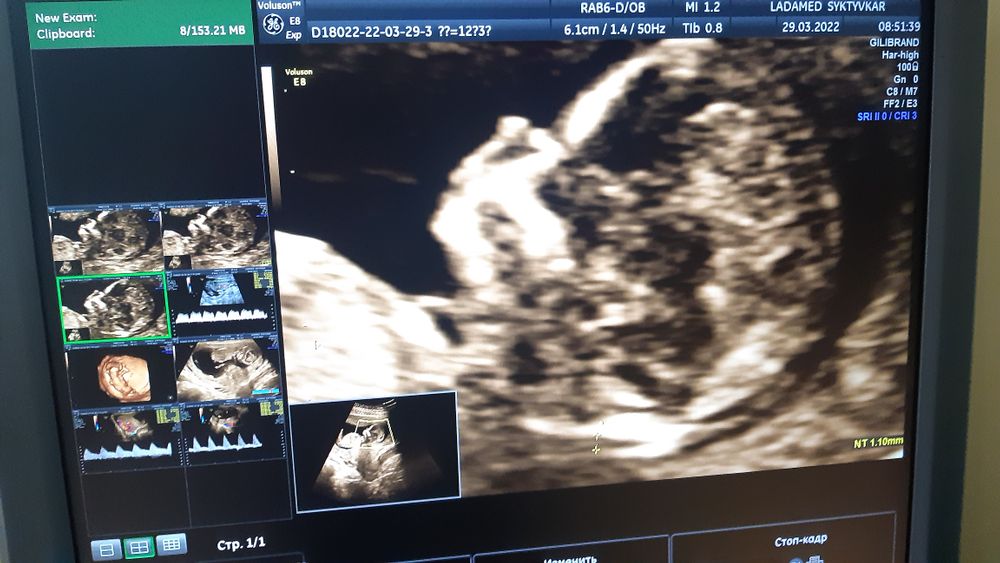

Сегодня сходила на первый скрининг, по узи, сказали, всё хорошо. По м срок 12+3, по ктр 12+6, ТВП 1,55, БПД 20, нк визуализируется 1,9

Врач предположила мальчика, но сказала, что лучше ещё перепроверить попозже.

В начале узи малыш спал, я даже испугалась, почему такой спокойный, но потом как заактивничал, что она его еле ловила, чтобы всё основательно проверить)) но посмотрели всё со всех сторон, даже увидели, как сжимает и разжимает свои крохотные пальчики😍